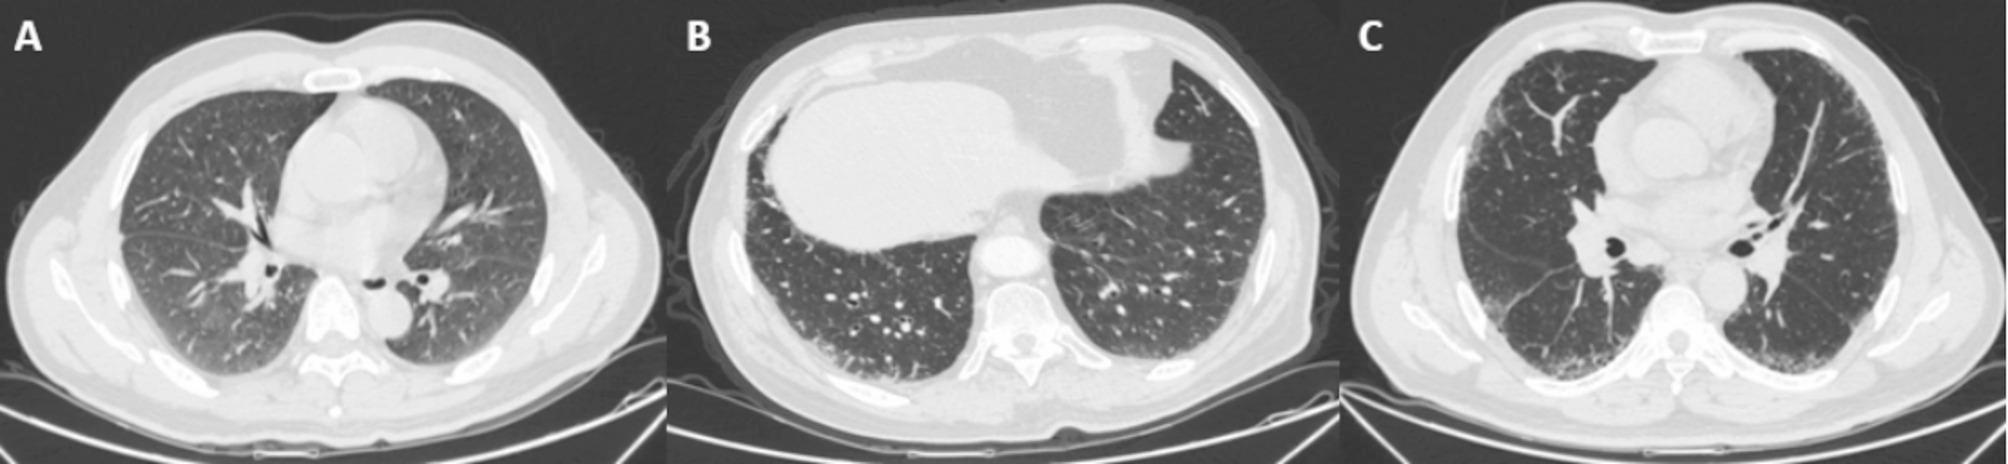

The standard approach to diagnosing idiopathic pulmonary fibrosis (IPF) includes identifying the usual interstitial pneumonia (UIP) pattern via high resolution computed tomography (HRCT) or lung biopsy and excluding known causes of interstitial lung disease (ILD). However, limitations of manual interpretation of lung imaging, along with other reasons such as lack of relevant knowledge and non-specific symptoms have hindered the timely diagnosis of IPF. This review proposes the definition of early IPF, emphasizes the diagnostic urgency of early IPF, and highlights current diagnostic strategies and future prospects for early IPF. The integration of artificial intelligence (AI), specifically machine learning (ML) and deep learning (DL), is revolutionizing the diagnostic procedure of early IPF by standardizing and accelerating the interpretation of thoracic images. Innovative bronchoscopic techniques such as transbronchial lung cryobiopsy (TBLC), genomic classifier, and endobronchial optical coherence tomography (EB-OCT) provide less invasive diagnostic alternatives. In addition, chest auscultation, serum biomarkers, and susceptibility genes are pivotal for the indication of early diagnosis. Ongoing research is essential for refining diagnostic methods and treatment strategies for early IPF.